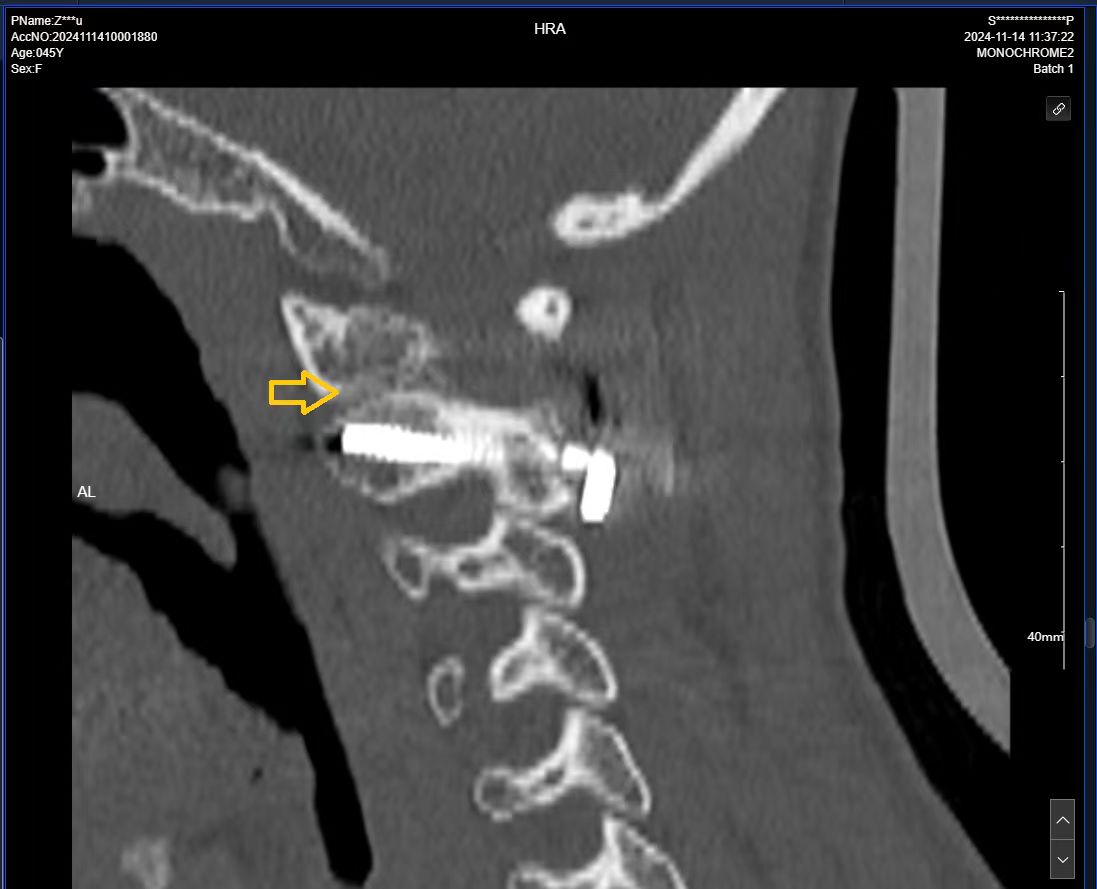

• 术后影像: